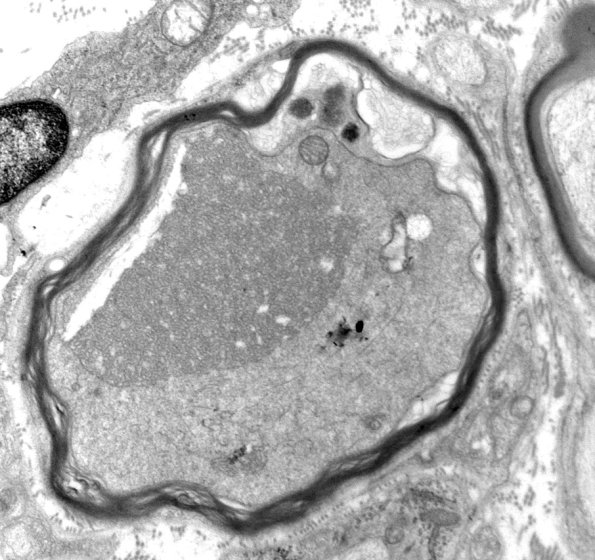

There does appear to be unmyelinated axon loss in this nerve and, surprisingly, there are numerous dystrophic axons with compact tubulovesicular elements. (electron micrographs)